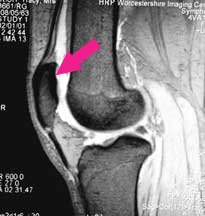

Here is an MRI scan, looking at the knee bones from the side, and where contrast has been reversed so that the bones are dark. You can recognise the rounded ends of the femur and the flattened top of the tibia.

The patella (red arrow) is quite peculiar. It is located right in the middle of the tendon of the quadriceps muscle, the muscle which forms most of your 'lap'- the tendon being the bit at the lower end where the muscle attaches to the tibia. From inside the joint only the undersurface of the patella is visible. The tendon above and below lies ouside the joint lining and cannot be seen.

The arrow shows you the undersurface of the patella. You can see how it only its undersurface projects into the joint cavity (white). Any idea what that triangular grey mass is which is projecting into the knee joint below the patella?

Did you get it? If so, well done. It is the fat pad.